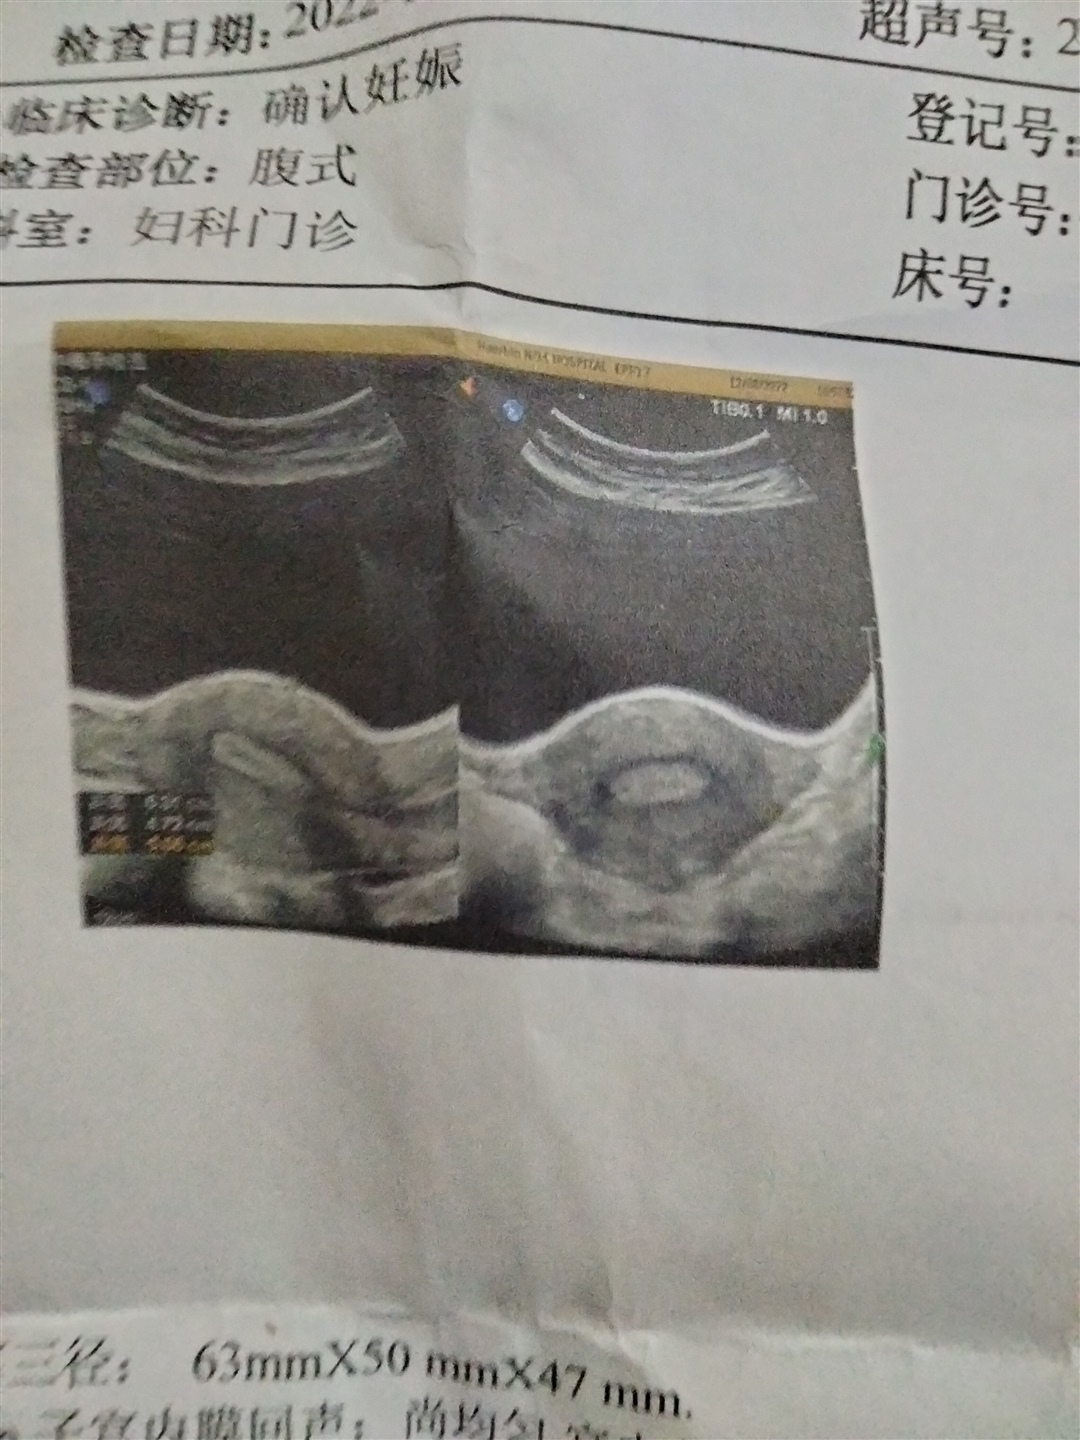

备孕中